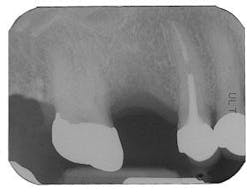

Figure 7 - Extraction Tooth No. 3 / Perioglas graft

Figure 8 - Healed bone graft Tooth No. 3